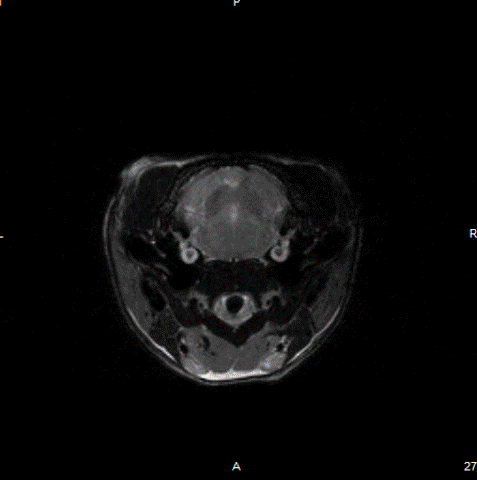

Cardiac Cine loop images: Long axis view of a single slice of the heart was acquired with Cine loop images. Long-axis images can be used for strain analysis in third-party software. Image Credit: Scintica Instrumentation Inc

Short axis view of a single slice of the heart was acquired with Cine loop images. Short axis images can be used to analyze functional measurements in third-party software. Image Credit: Scintica Instrumentation Inc